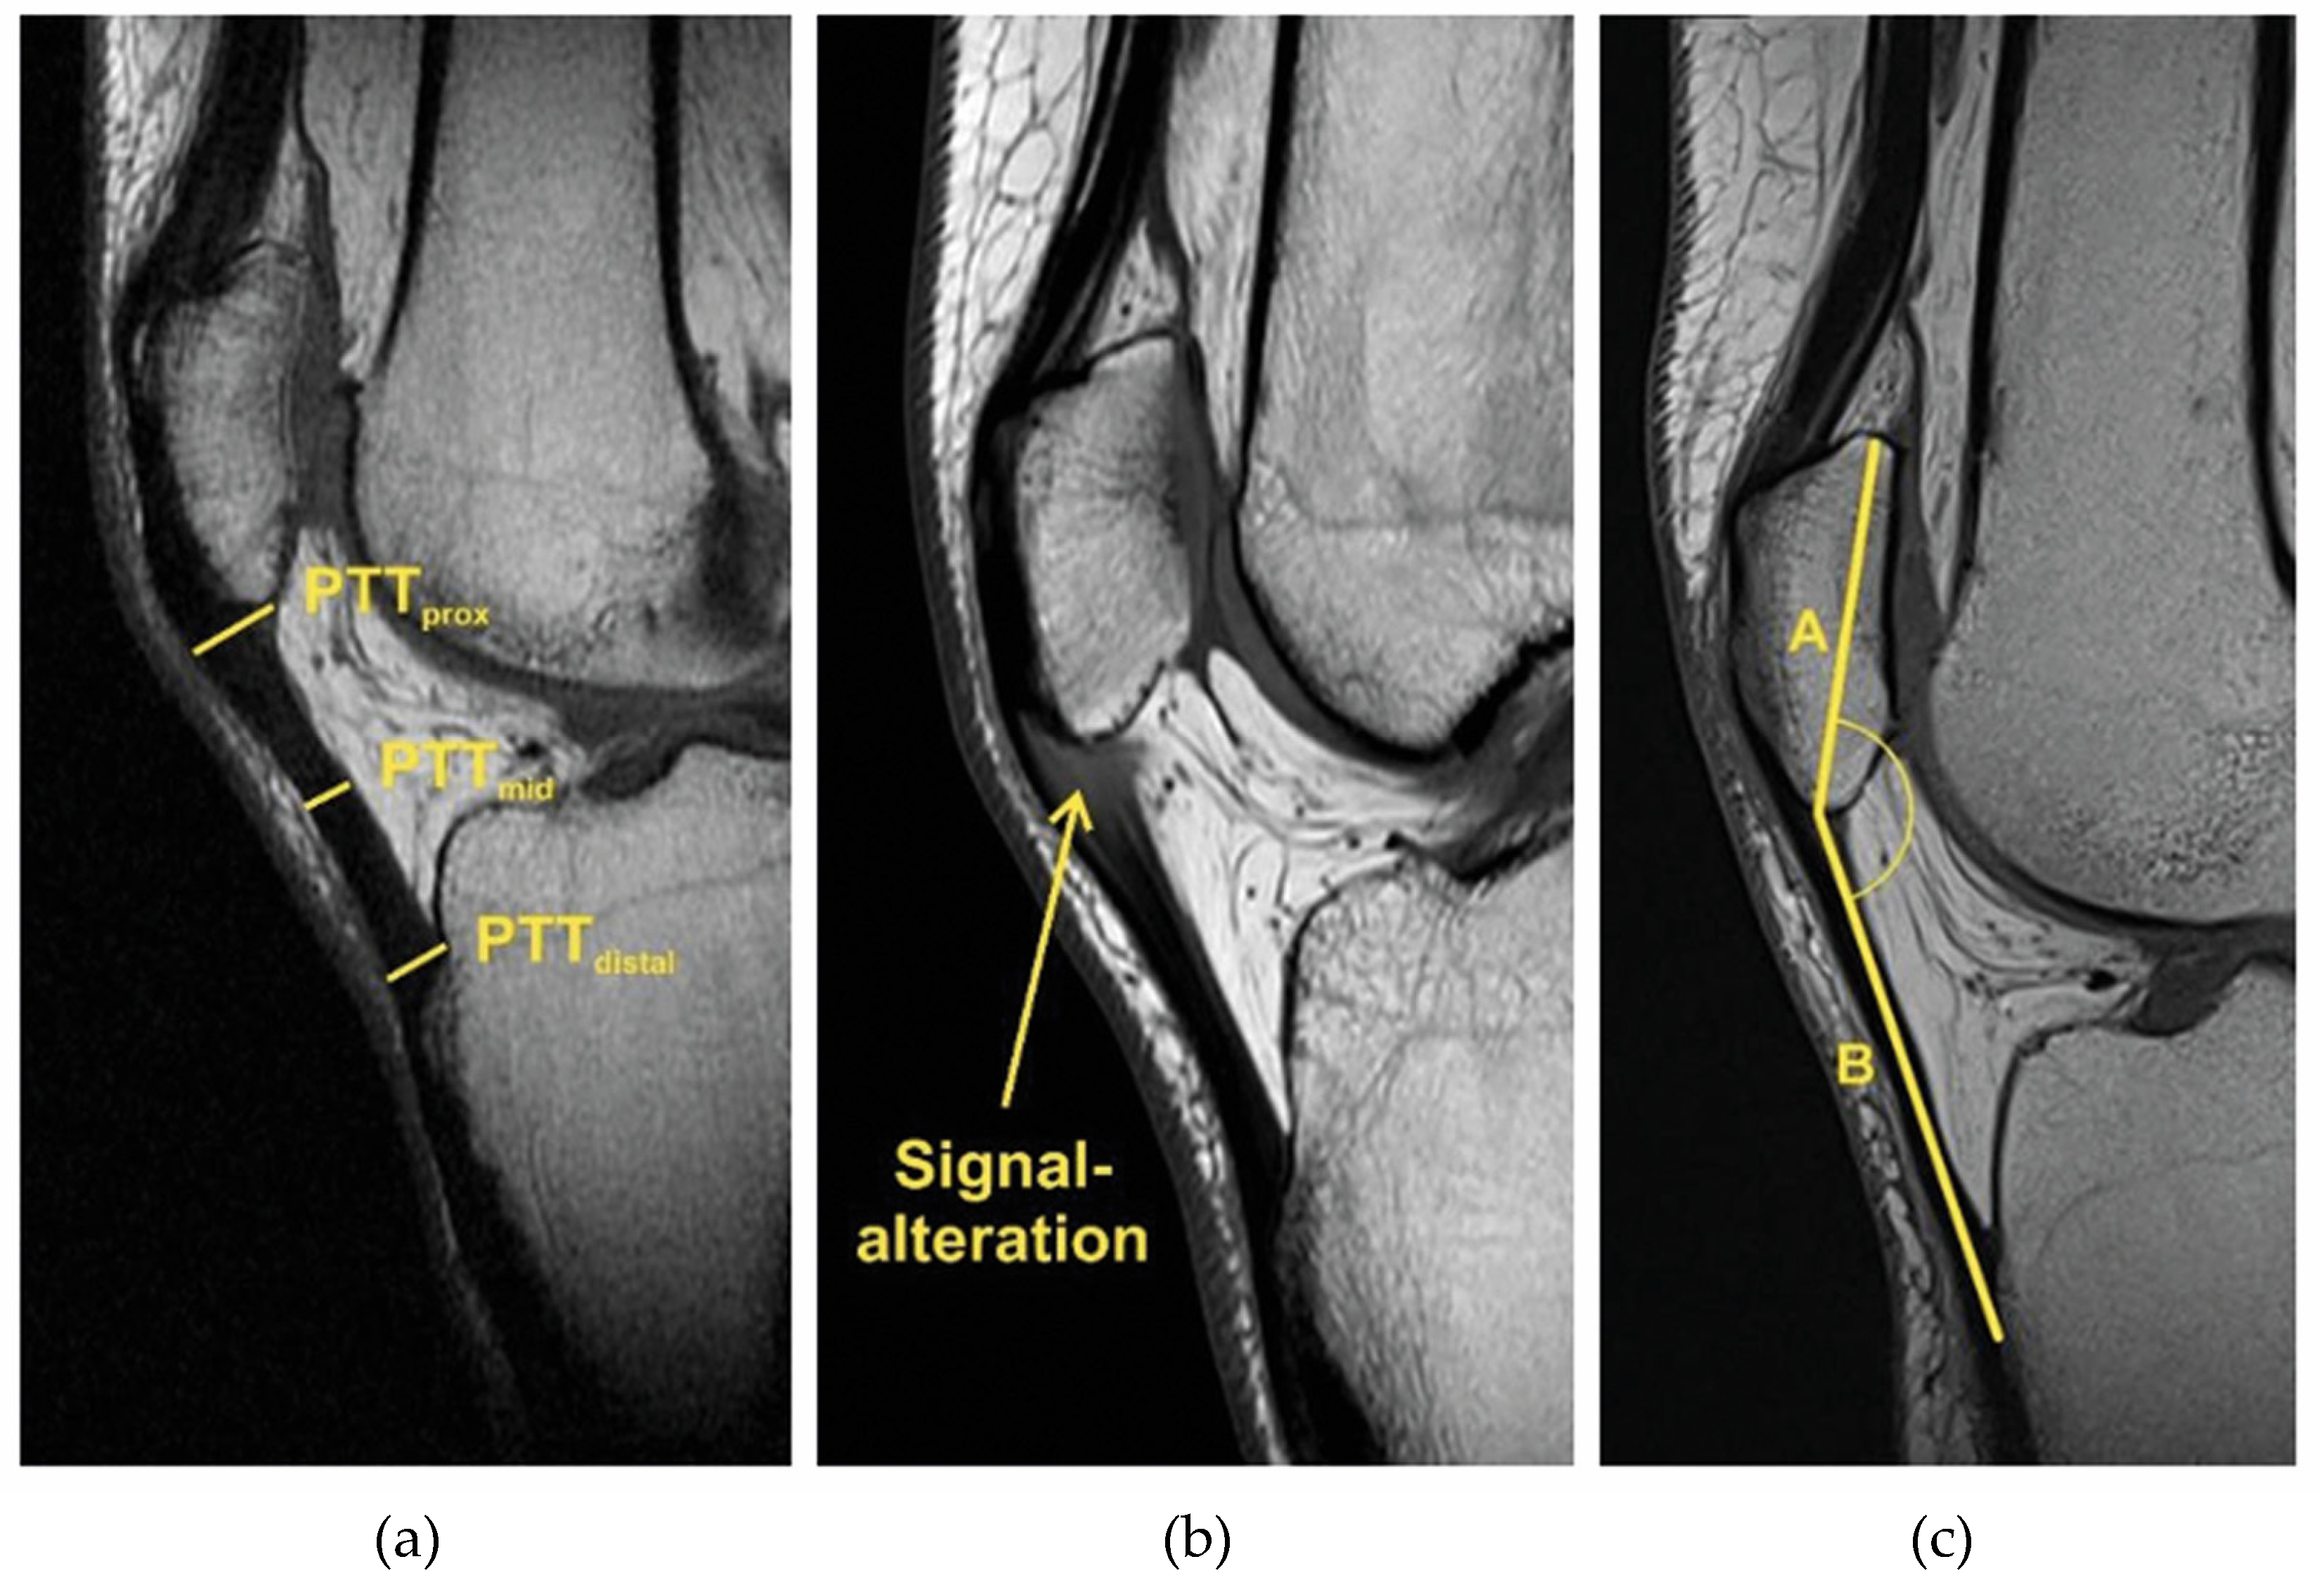

Patellar tendon thickness (PTT) was measured in the sagittal plane on the MRI image with the greatest distance between the base patella and apex patella. Tendon thickness was measured proximally at the origin of the tendon (PTTprox), distally at the insertion at the tibial tuberosity (PTTdistal) and at the midpoint of these two points (PTTmid) (Figure 4a). In the same image, the presence of signal intensity was also checked (Figure 4b). The patella–patellar tendon angle (PPTA) measures the angle between the line drawn from the base of the patella to the apex (A) and the line drawn between the apex of the patella to the insertion of the patellar tendon on the tibial tuberosity (B) (Figure 4c).

Figure 4.

(a) Patellar tendon thickness (PTT): shown here on MRI, a thickened patellar tendon with PT in the proximal (PTTprox), middle (PTTmid) and distal segments (PTTdistal). (b) Signal intensity (alteration) in PT at the origin of the patellar tendon. (c) Patella–patellar tendon angle (PPTA): angle between the line drawn from the base of the patella to the apex (A) and the line drawn between the apex of the patella to the insertion of the patellar tendon on the tibial tuberosity (B).